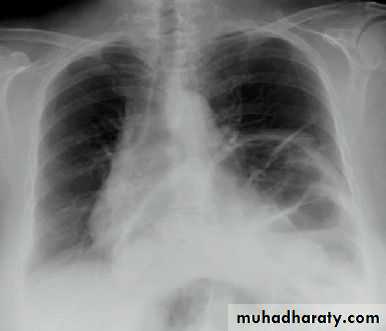

What is the difference?

(emphysematous bullae) (pneumothorax)

(Collapse) (Massive plural effusion)